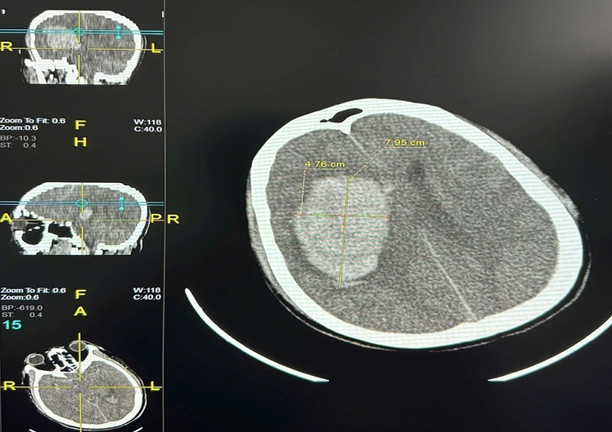

Một trường hợp khác, người đàn ông 45 tuổi, ở Hà Nội tiền sử khoẻ mạnh, sau tắm khuya cũng đau đầu, đến viện trong tình trạng hôn mê. Kết quả chẩn đoán cho thấy xuất huyết não với khối máu 90 cm3. Bác sĩ buộc phải chỉ định phẫu thuật mở sọ để giải ép áp lực não. Hiện bệnh nhân vẫn phải điều trị tích cực, duy trì thở máy, tiên lượng rất nặng.

Hình ảnh phim chụp cho thấy khối máu tụ bán cầu phải với thể tích khoảng 90 cm3. (Ảnh: BVCC)